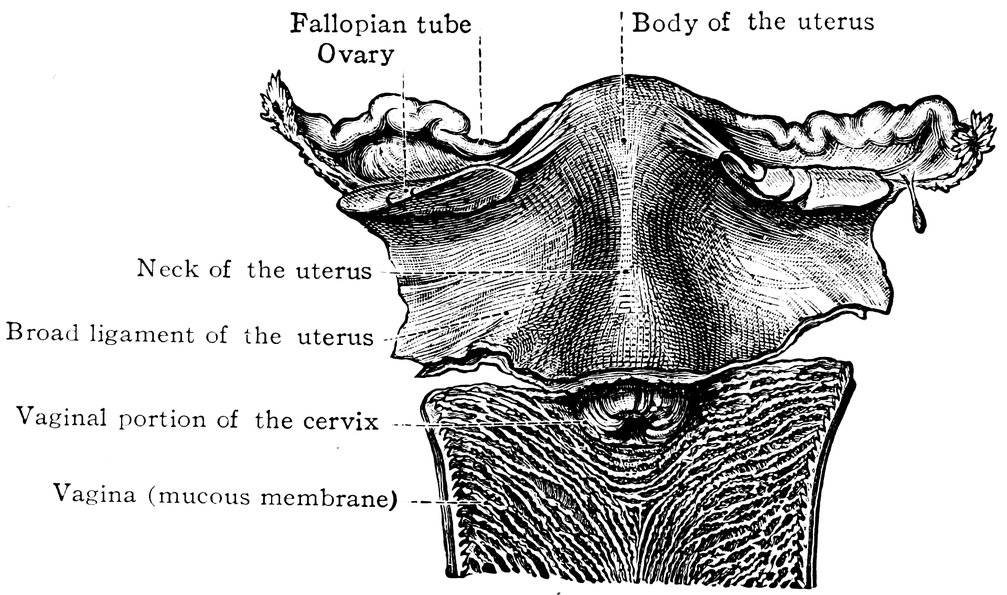

| 2. | Portion of the pelvic viscera in the female, etc. | 9 |

| 51. | Female internal genital organs in the fully developed state | 208 |

Quite as significant, moreover, as the changes in the ovaries, are those which, in the course of the sexual life, the uterus undergoes, in shape and size, in its muscular substance and mucous lining, and in its vascular and nervous supply.

Fig. 2.—Portion of the pelvic viscera in the female, and their relation to the muscles of the pelvic outlet (or perineal muscles), shown in the left half of the pelvis, seen from the right side.—The parametrium. (From Toldt: Atlas of Human Anatomy.—Rebman Company, New York.)

10At the time of puberty the infantile uterus undergoes changes affecting both its external form and the shape of its interior cavity. The body of the uterus enlarges to the size characteristic of sexual maturity, and its mucous membrane becomes the seat of periodic changes. This waxing and waning growth and transformation of the uterine mucous membrane continues throughout the period of menstrual activity, the most superficial layers of the membrane being shed during menstruation, a process followed by regeneration, which is itself succeeded by the premenstrual thickening. When conception occurs, still more extensive changes ensue, the fertilized ovum becoming imbedded in the uterine mucous membrane, and the pregnant uterus, in shape and structure and in the respective relations of the body and neck of the organ, in the increasing distension of its veins and the increasing size of its nerves, becoming adapted to the important functions it has now to fulfil. When these have been fulfilled, and, parturition having taken place, the uterus is empty once more, the organ again adapts itself to altered circumstances by the process of involution. Later, in the climacteric period, a slow regressive process occurs, the outward manifestation of which is the cessation of the menstrual flow, characterized anatomically by atrophy of the muscular tissue of the uterus and of its vascular apparatus, by the dessication of its mucous membrane, by obliteration of the lumen of the uterine cavity, and ultimately by senile degeneration and atrophy of the now entirely functionless organ, so that it becomes an insignificant, cicatrized, solid body.